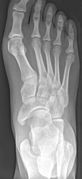

Os tibiale externum - Roe Fuss.jpg

X-ray of the foot showing an accessory navicular bone